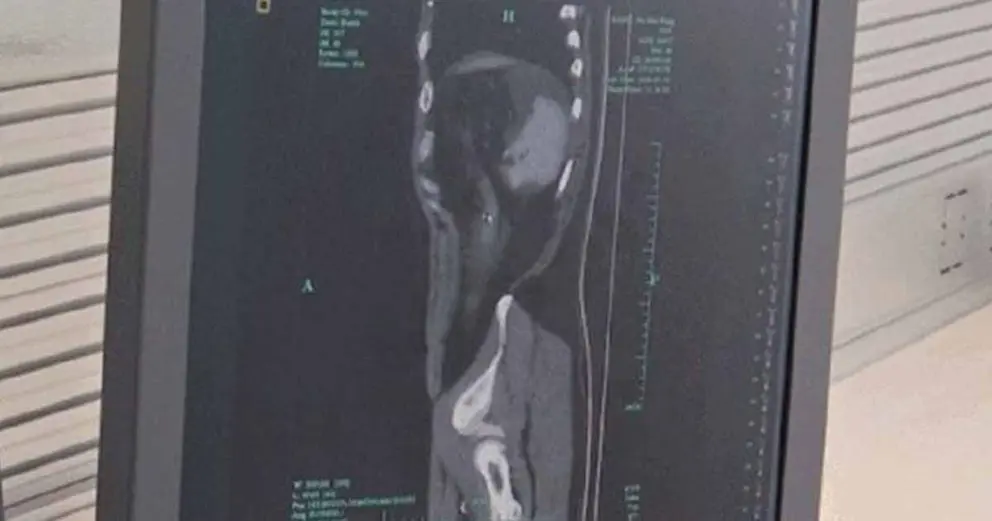

De inmediato tuvo que ser ingresado en el Hospital Popular Zhuji en Zhejiang, al este de China, donde una tomografía computada reveló que su vejiga había reventado en tres partes. Los médicos calificaron las lesiones como peligrosas. Potencialmente. Tanto es así que incluso se temía por su vida.